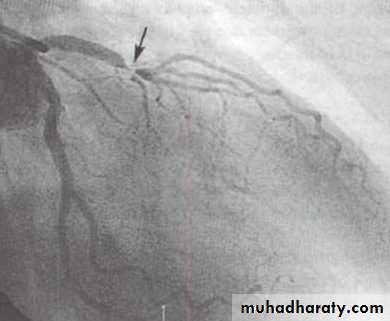

Coronary arteriography

Coronary AngiographyFor more presentations www.medicalppt.blogspot.com